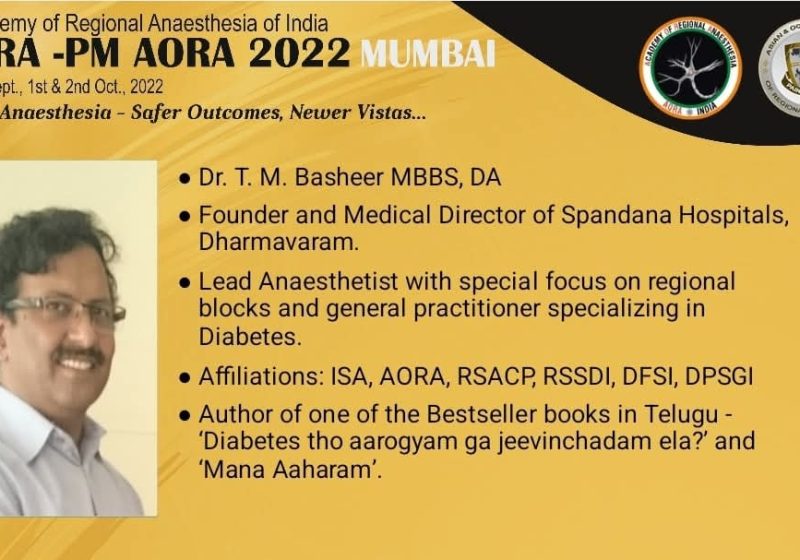

- Awards and Honors

- Books written by Dr Basheer